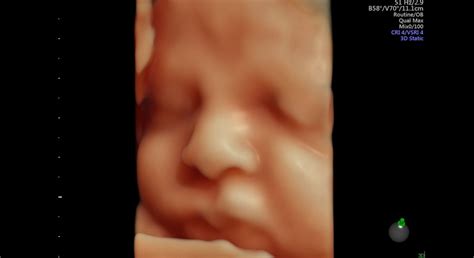

3D a 4D ultrazvuk

Okrem bežného dvojrozmerného ultrazvuku existujú aj pokročilejšie techniky ako 3D a 4D ultrazvuk. 3D ultrazvuk zobrazuje dieťatko trojrozmerne, čo umožňuje rodičom vidieť jeho tvárové črty a podobu. 4D ultrazvuk pridáva tretí rozmer v reálnom čase, takže je možné vidieť pohyb dieťatka. Tieto vyšetrenia sú obľúbené, aj keď majú svoje limity a nie vždy je obraz úplne zreteľný. Lekár vám môže z takéhoto vyšetrenia zvyčajne natočiť video alebo vytlačiť 3D fotografiu dieťatka.